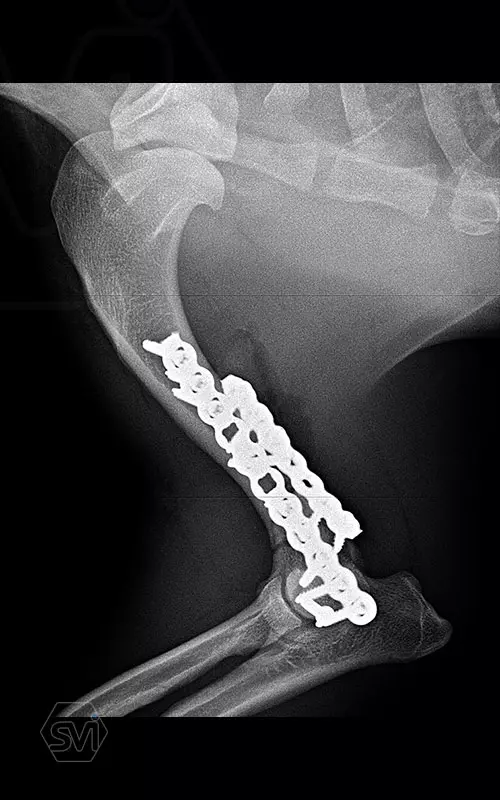

In our first case, we got right to the heart of it: we operated on a 2-year-old dachshund-type mixed dog weighing 9 kg, who overstretched his right humerus while stepping on pallets and suffered a Y-shaped humerus fracture that extended into the elbow joint combined with a large longitudinal splinter. To treat the fracture, we chose the new, cutable poliaxial locking plate, and immediately placed two, one medially and one caudolaterally. The intercondylar fracture and the longitudinal diaphysis fragment were each fixed with a 2.4 lag screw.

The ability to transition between sizes (2.0-2.4) was very useful. We positioned the plate with thinner (2.0 mm) cortical screws, the fragments were fitted to each other, and after the final state was established, we further stabilized the system with the locking screws placed in the empty holes, and then the thinner cortical screws were also replaced with thicker locking ones.

The plate behaved very well, it was much easier to work with than the straight plates used so far, it was easy to cut to size and shape it on the curved dachshund bone.

The advantage of polyaxiality proved to be particularly useful here, where it is very easy to drive the screw into the joint! There is no need to talk about the advantages of lockig systems around the elbows, where the pulling and stretching forces are magnified.

TIP: On the medial side, the very short screw above the fracture line was only used as a "blind plug" so that the hole would not remain without a screw, and the plate would not have a weak point above the fracture.More information: